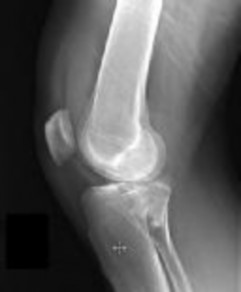

Figures 1 and 2 are the radiographs of a 35-year-old man who is brought into the emergency department after a motor vehicle collision. He is complaining of isolated knee pain. Examination reveals swelling, blood filled blisters, popliteal ecchymosis, joint line pain, and limited knee joint motion. His pulses and sensation are normal.

This knee injury is best described as a